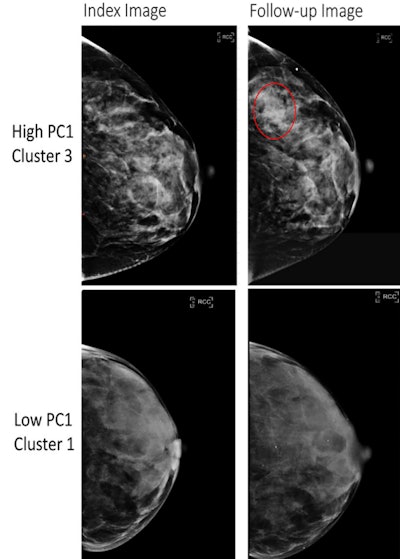

Full-field digital mammography (FFDM) images in a 52-year-old woman show a high-risk phenotype (top), and FFDM images in a 58-year-old woman show a low-risk phenotype (bottom). The high-risk phenotype was defined by having high values of the first principal component (PC1) and was assigned to cluster 3 (top row), and the low-risk phenotype was defined by having low values of the PC1 and was assigned to cluster 1 (bottom row). The index images (left side; before any diagnosis of cancer) are provided as well as follow-up images obtained at either the time of cancer diagnosis (for the high-risk phenotype, top right) or at the last follow-up (low-risk phenotype, bottom right). The red circle indicates the location of subsequent breast cancer. Both women had a BI-RADS breast density of C. The woman at high risk for breast cancer was Black and the woman at low risk for breast cancer was white.Full-field digital mammography (FFDM) images in a 52-year-old woman show a high-risk phenotype (top), and FFDM images in a 58-year-old woman show a low-risk phenotype (bottom). The high-risk phenotype was defined by having high values of the first principal component (PC1) and was assigned to cluster 3 (top row), and the low-risk phenotype was defined by having low values of the PC1 and was assigned to cluster 1 (bottom row). The index images (left side; before any diagnosis of cancer) are provided as well as follow-up images obtained at either the time of cancer diagnosis (for the high-risk phenotype, top right) or at the last follow-up (low-risk phenotype, bottom right). The red circle indicates the location of subsequent breast cancer. Both women had a BI-RADS breast density of C. The woman at high risk for breast cancer was Black and the woman at low risk for breast cancer was white.RSNA